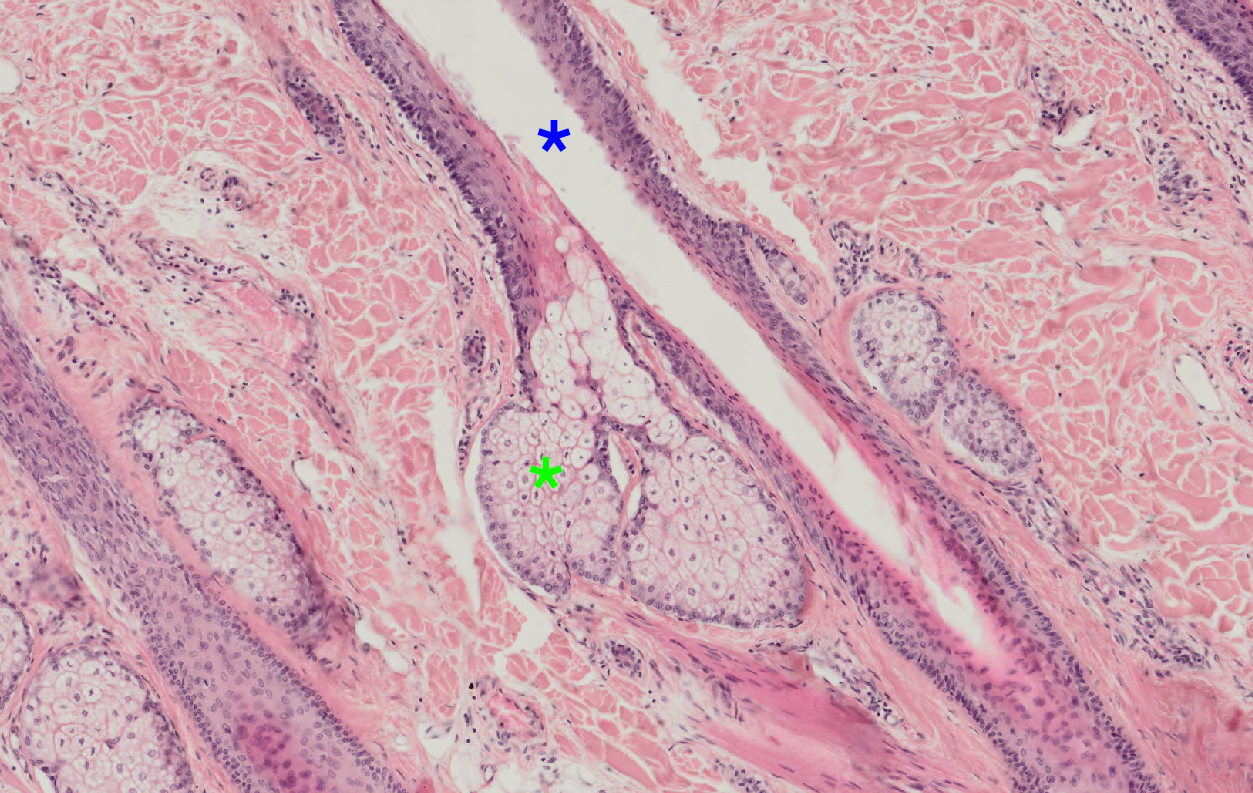

12 On the picture of thin type of skin (hematoxylin eosin), green asterisk denotes a sebaceous gland. Which structure is labeled by blue asterisk? Skin Sebaceous.png

Ductus of a sebaceous gland

Ductus of a sweat gland

Hair follicle

Artifact